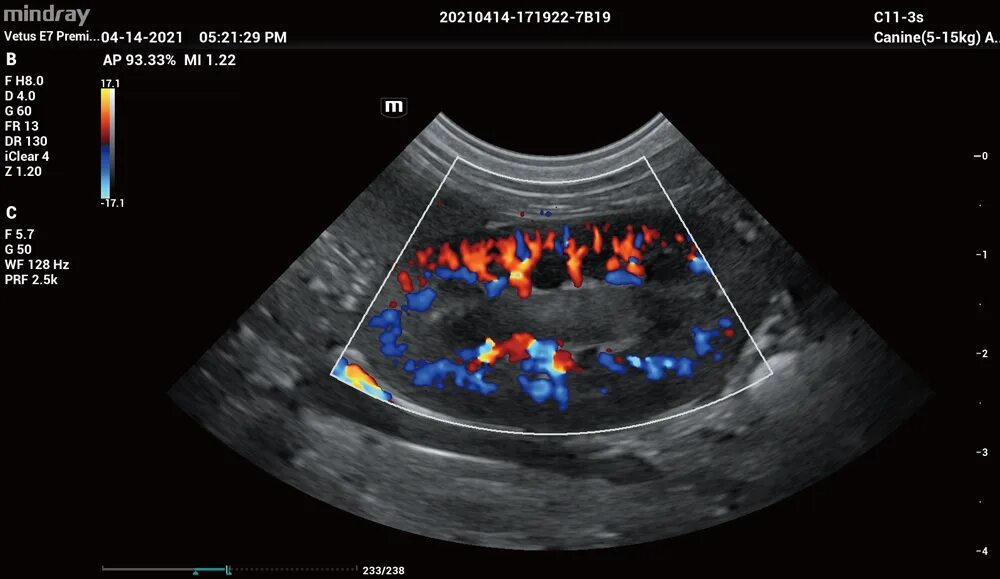

Mindray vetus